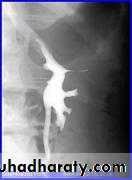

Pelviureteric junction obstruction

This condition has a spectrumof severity from severe antenatal hydronephrosis with global cortical loss to radiologically demonstrable hydronephrosis in theadult without apparent symptoms or loss of renal functionUp to 20%are associated with an accessory renal artery running across thePUJ, which may be visible on the IVU as a smooth indentation.

During the acute episode there are features on IVU of severe acute obstruction, which include a delayed, increasingly dense nephrogram and delayed appearance (sometimes up to 24 h or more) of contrast within the collecting system. When opacification occurs it demonstrates clubbed calyces and a dilated pelvis